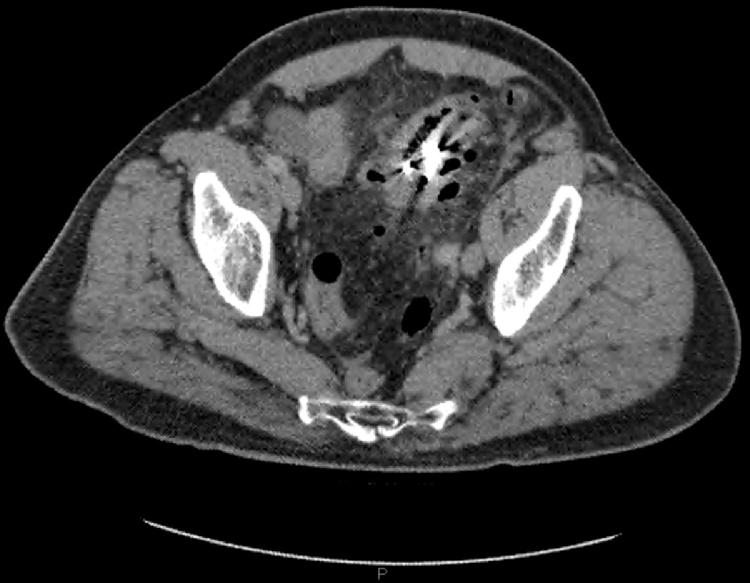

Rare case of an elderly male presenting to the emergency department with an acute abdomen few days post accidental ingestion of his dentures. A detailed history along with a CT abdomen showed perforation in the sigmoid colon adjacent to the site of the swallowed denture.

一名老年男性在意外吞食假牙几天后因急腹症就诊于急诊科,这种情况较为罕见。详细病史及腹部CT显示,乙状结肠在吞食假牙部位附近出现穿孔。